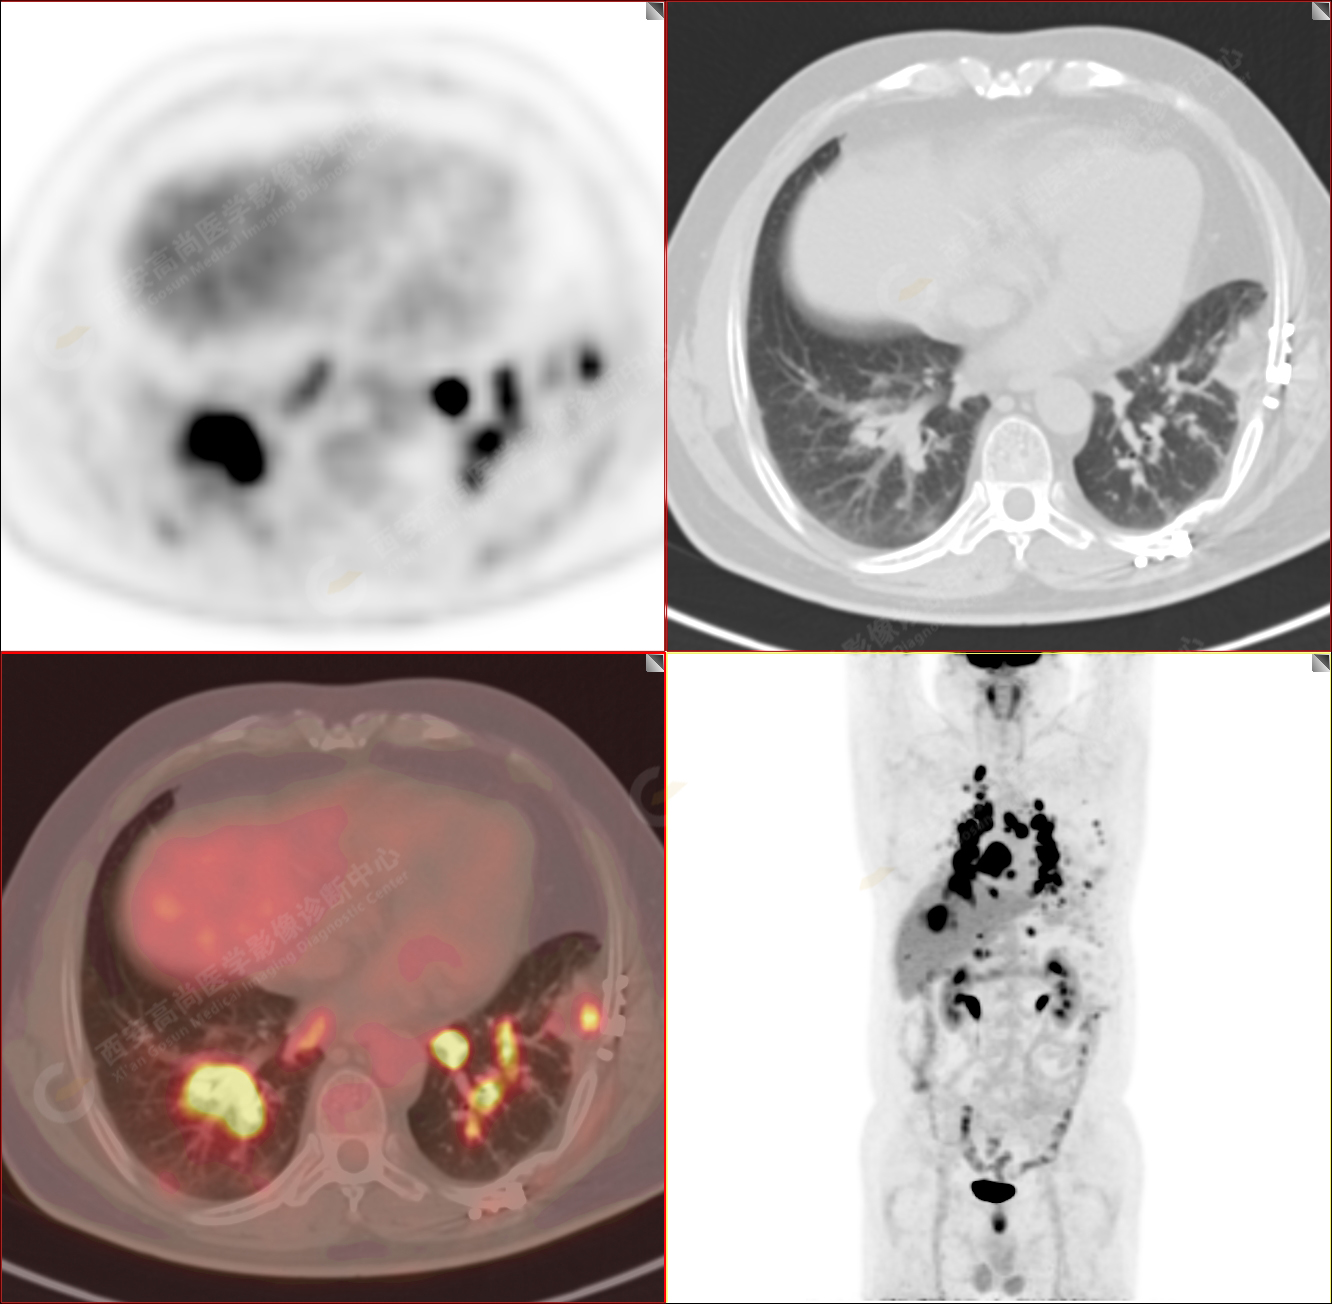

男性,53歲,頭暈半月入院,CT發(fā)現(xiàn)肺內(nèi)腫塊,雙肺多發(fā)大小不等實(shí)性及粟粒樣結(jié)節(jié),雙肺門(mén)及縱隔多發(fā)腫大淋巴結(jié)。病程中無(wú)發(fā)熱、胸悶氣及胸部不適。既往:左側(cè)肋骨外傷史。

PET/CT圖像